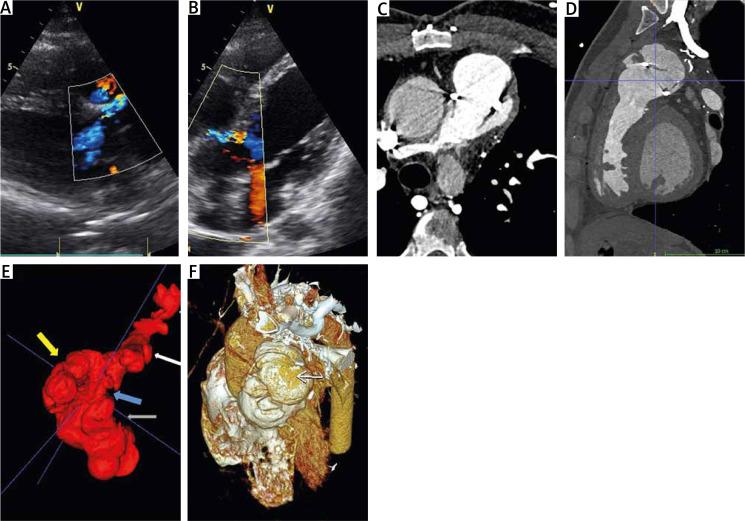

Recurrent pulmonary artery pseudoaneurysm in a patient with tetralogy of Fallot.